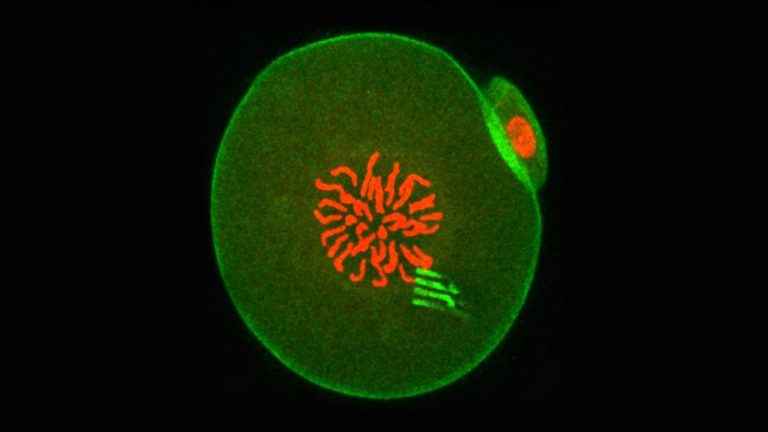

این تحقیق به سرپرستی پروفسور تونی پری از گروه زیست‌شناسی و زیست‌شیمی دانشگاه باث انجام شده است. در این تحقیق یک نانوابزار مبتنی بر سیلیکون به همراه اسپرم وارد تخمک موش شد تا فرآیند تقسیم و رشد سلولی را تحت نظر بگیرد. نتیجه این آزمایش یک تخمک بارور شده و سالم، ولی حاوی یک دستگاه ردیابی بود.

این نانوابزارها کمی شبیه به عنکبوت هستند؛ هشت پا دارند و بسیار منعطف هستند. پاهای این نانوابزار به راحتی می‌تواند کشش و فشار اعمال شده در داخل سلول را با دقت بسیار بالایی اندازه‌گیری کند و در نتیجه نیروهای سلولی در حین رشد را به خوبی نشان می‌دهد و تشریح می‌کند که چگونه ماده درون سلولی خود را با گذشت زمان دوباره تنظیم می‌کند.

این نانوابزار یا بهتر بگوییم نانوروبات بسیار بسیار ریز و شبیه به برخی از اجزای سازنده سلول است. اندازه آن ۲۲ نانومتر و تقریبا ۱۰۰ هزار بار نازک‌تر از یک سکه یک پوندی است. در تیجه انعطاف‌پذیری لازم را برای حرکت داخل سلول دارد و می‌تواند حرکت سیتوپلاسم سلول به عنوان جنین تک سلولی را دارد و می‌تواند سفر خود را به سمت جنین دو سلولی نیز ادامه دهد.

اینکه جنین موش برای آزمایش محققان انتخاب شده است، به دلیل اندازه نسبتا بزرگ سلول‌های آن است. قطر این سلول‌ها ۱۰۰ میکرون یا ۱۰۰ میلیونیم متر است. این در حالی است که سلول‌ معمولی فقط ۱۰ میکرون است. این بدان معنی است که داخل هر سلول جنینی موش، جایی برای دستگاه ردیابی وجود دارد.

محققان اندازه‌گیری‌های خود را با بررسی ویدئوهای ثبت شده توسط میکروسکوپی انجام دادند که هنگام توسعه جنین وارد سلول می‌شود. پروفسور پری در این مورد می‌گوید: گاهی این ابزار به دلیل نیروهایی که حتی بیشتر از سلول‌های داخل ماهیچه است، پیچ و تاب می‌خورند. اما بعضی زمان‌ها، حرکت کمی دارند و این امر نشان می‌دهد فضای داخلی سلول آرام شده است.